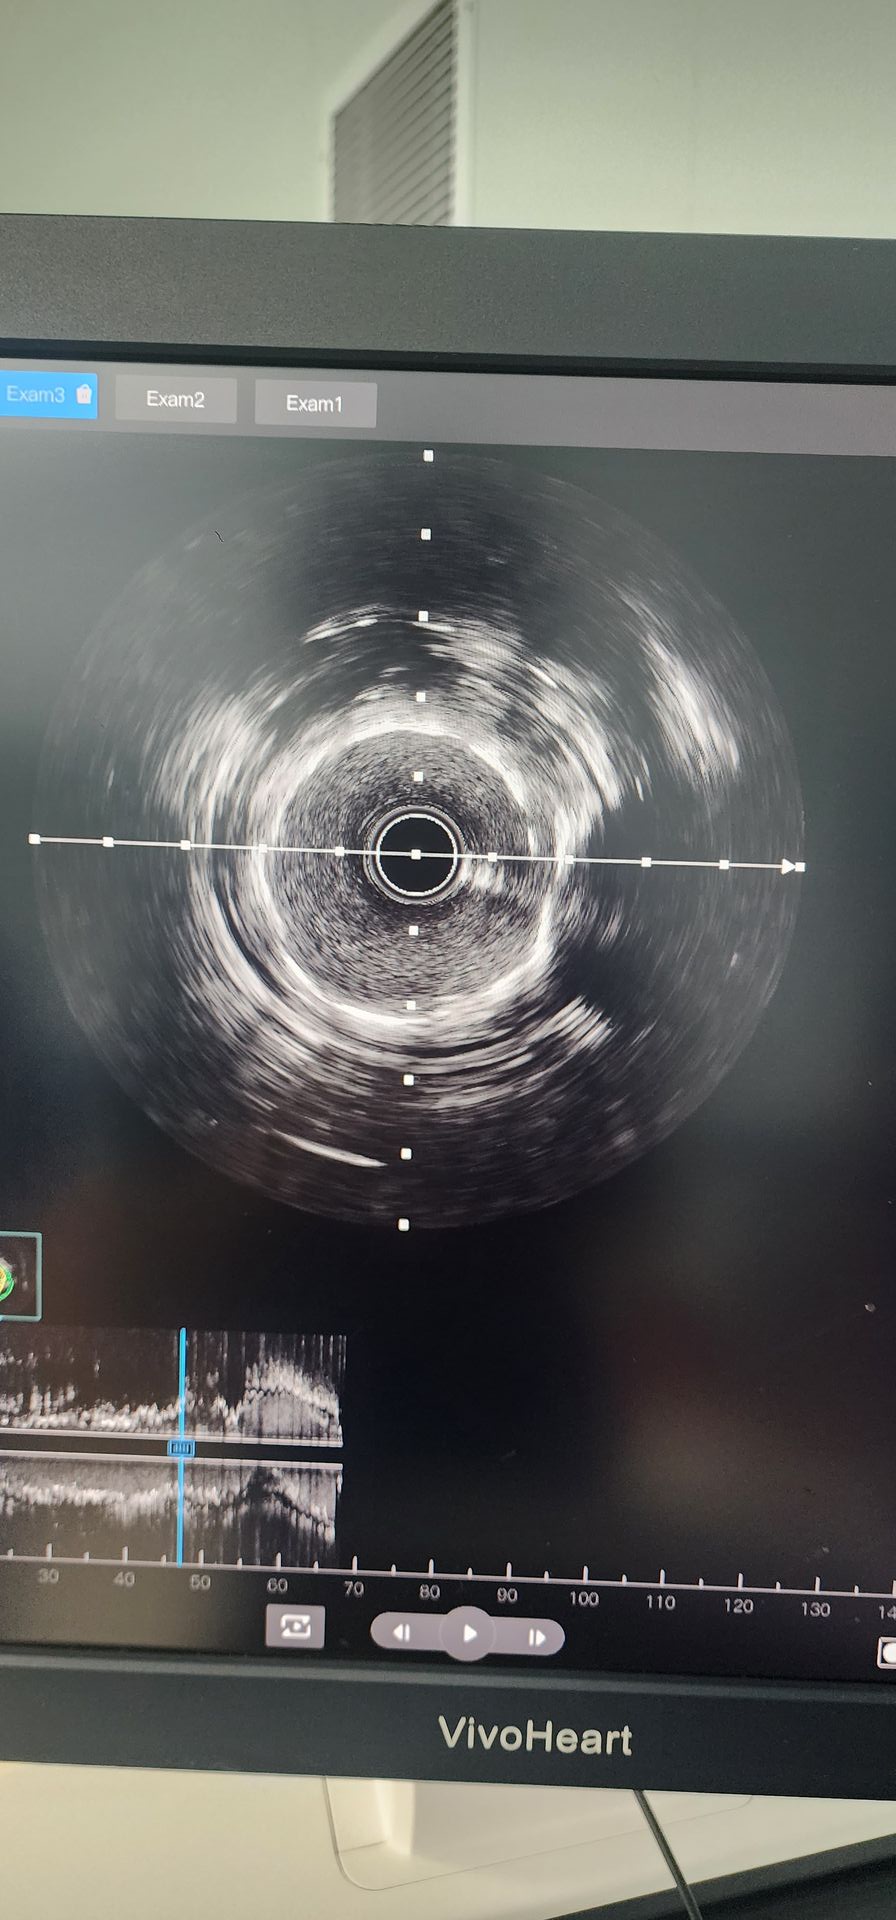

Angiografia wieńcowa wykazała silne zwapnienie z 95% zwężeniem tętnicy okołogwiętej bliższej i 85%-90% zwapninionym zwężeniem tętnicy wieńcowej środkowej prawej.

Słabe wyniki wykazała proksymalna cyrkulacyjna arteria: początkowa wstępna dylatacja z balonem 2,0 × 20. Następnie zastosowano cewnik balonowy 2,5 × 12 Lepu Vesscrack Coronary IVL Dilatation, dostarczając cztery cykle, z powodzeniem łamiąc zwapnianą zmianę. Po znacznej poprawie zwężenia z powodzeniem wszczepiono stent 2,5 × 14, z zadowalającymi wynikami angiograficznymi.

Mid-Right Coronary Artery: Początkowe wstępne rozszerzenie z balonem 2,5 × 20 spowodowało ograniczoną poprawę. Cewnik balonowy 2,5 × 12 Lepu Vesscrack wieńcowy IVL był następnie używany przez dwa cykle, znacznie poprawiając zwężenie zwapnianej zmiany. Następnie z powodzeniem wszczepiono stent 3,0 × 19, uzyskując zadowalające wyniki angiograficzne.